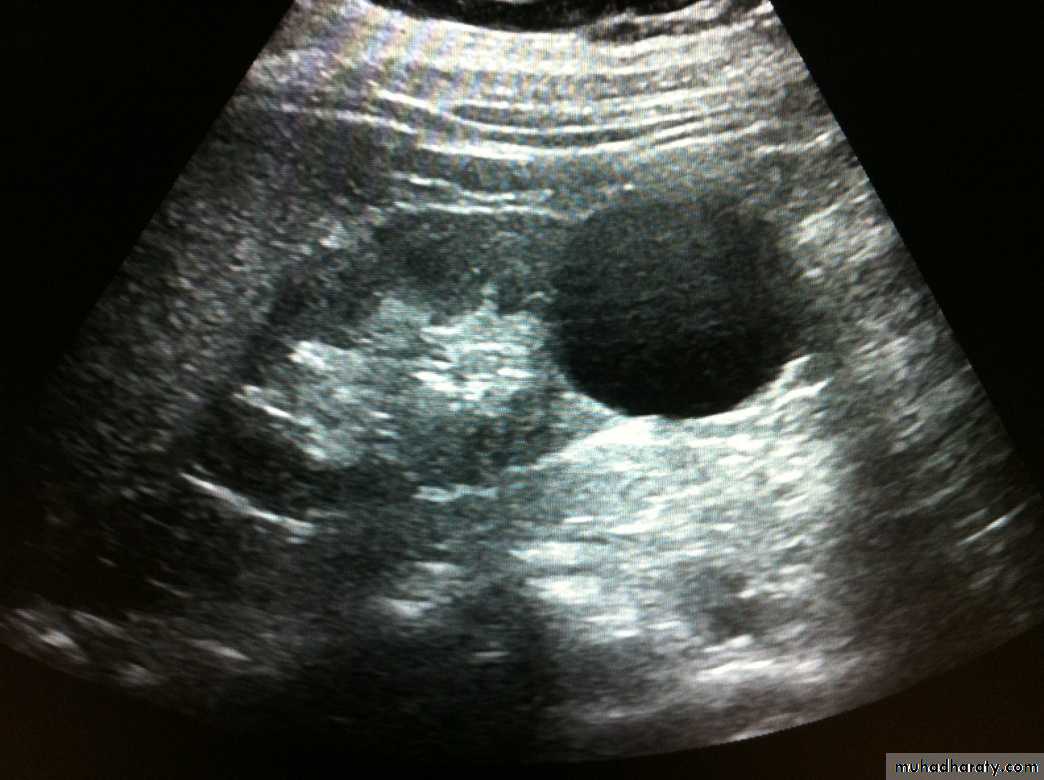

Simple renal cyst with acoustic enhancement